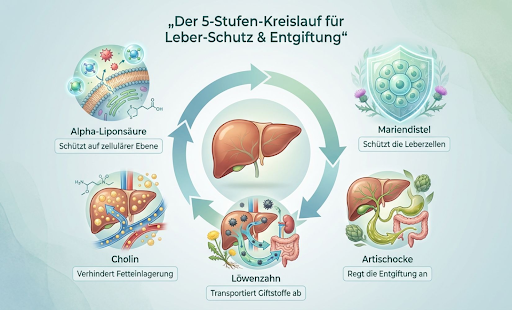

„Das Wichtigste ist Ebene 1 – da muss der Fett-Stau gelöst werden. Deine Leber braucht Cholin, damit sie überhaupt Fette abtransportieren kann. Dazu kommt Inositol, das mit dem Cholin zusammenarbeitet und die Insulinsensitivität verbessert. Und dann noch Alpha-Liponsäure – das schützt die Leberzellen, während sie die ganze Arbeit machen. Das ist das Fundament. Ohne das läuft nichts.“

„Dann brauchst du Ebene 2 – die Pflanzenstoffe. Mariendistel mit richtig viel Silymarin, nicht diese Mini-Dosen aus der Drogerie. Die schützt die Leberzellen wie eine Rüstung. Artischocke sorgt dafür, dass genug Galle produziert wird für die Fettverdauung. Und Löwenzahn mit Wermut – das sind Bitterstoffe, die die ganze Verdauung ankurbeln. Diese Ebene schützt deine Leber, während sie auf Hochtouren läuft.“

„Und schließlich Ebene 3 – die Struktur. Da kommt Silizium ins Spiel, aus Bambus-Extrakt. Das stärkt die Zellstrukturen langfristig. Wie das Stahlgerüst in einem Gebäude – ohne stabiles Gerüst bricht irgendwann alles zusammen, egal wie gut der Rest ist.“

Wir haben die 5 wissenschaftlichen Studien geprüft, auf die sich das 3-Ebenen-System stützt:

Studie 1: Artischocke hilft der Leber Wissenschaftler untersuchten 7 verschiedene Studien mit insgesamt hunderten Patienten. Das Ergebnis: Artischocke senkt die Leberwerte (ALT und AST) deutlich – besonders bei Menschen mit Fettleber. Höhere Dosen (über 500mg) wirkten am besten.

Studie 2: Ohne Cholin entsteht Fettleber Forscher fanden heraus: Wenn Menschen zu wenig Cholin bekommen, lagert ihre Leber Fett ein – selbst bei gesunden, schlanken Personen. Das passierte schon nach 6 Wochen. Cholin ist der Schlüssel, damit die Leber Fett abtransportieren kann.

Studie 3: Mariendistel schützt Leberzellen Eine große Übersichtsarbeit zeigte: Silymarin (der Wirkstoff aus Mariendistel) schützt die Leber vor Schäden durch Alkohol, Gifte und Entzündungen. Es wirkt wie ein Schutzschild für die Leberzellen.

Studie 4: Inositol reduziert Leberfett In Tier- und Humanstudien senkte Inositol das Fett in der Leber deutlich. Auch Triglyceride und Leberenzyme verbesserten sich. Es arbeitet gut mit Cholin zusammen.

Studie 5: Alpha-Liponsäure schützt während der Arbeit Diese Studie zeigte: Alpha-Liponsäure ist ein starkes Antioxidans, das die Leber vor oxidativem Stress schützt – besonders während sie Fette verarbeitet. Es wurde erfolgreich bei verschiedenen Leberschäden eingesetzt.

83mg Cholin, 200mg Inositol, 90mg Alpha-Liponsäure. 200mg Silymarin aus Mariendistel – und eben nicht die lächerlichen 50mg aus der Drogerie. Artischocke, Löwenzahn, Wermut, Silizium. Alles drin. Alles richtig dosiert.